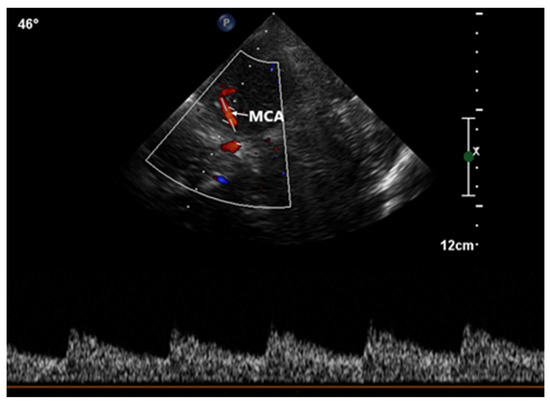

2.2.2. Contrast-Enhanced TCCD